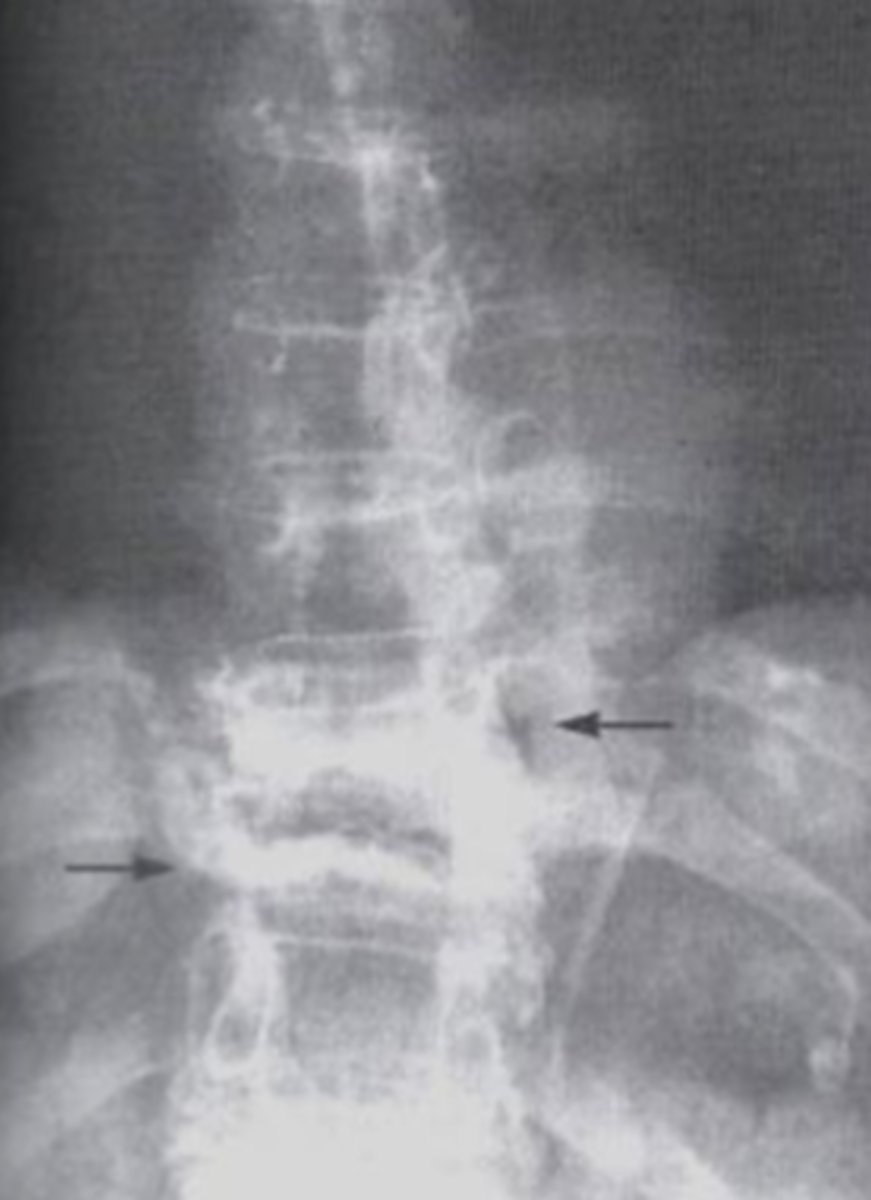

ankylosing spondylitis

What is the issue?

Spondylolysis